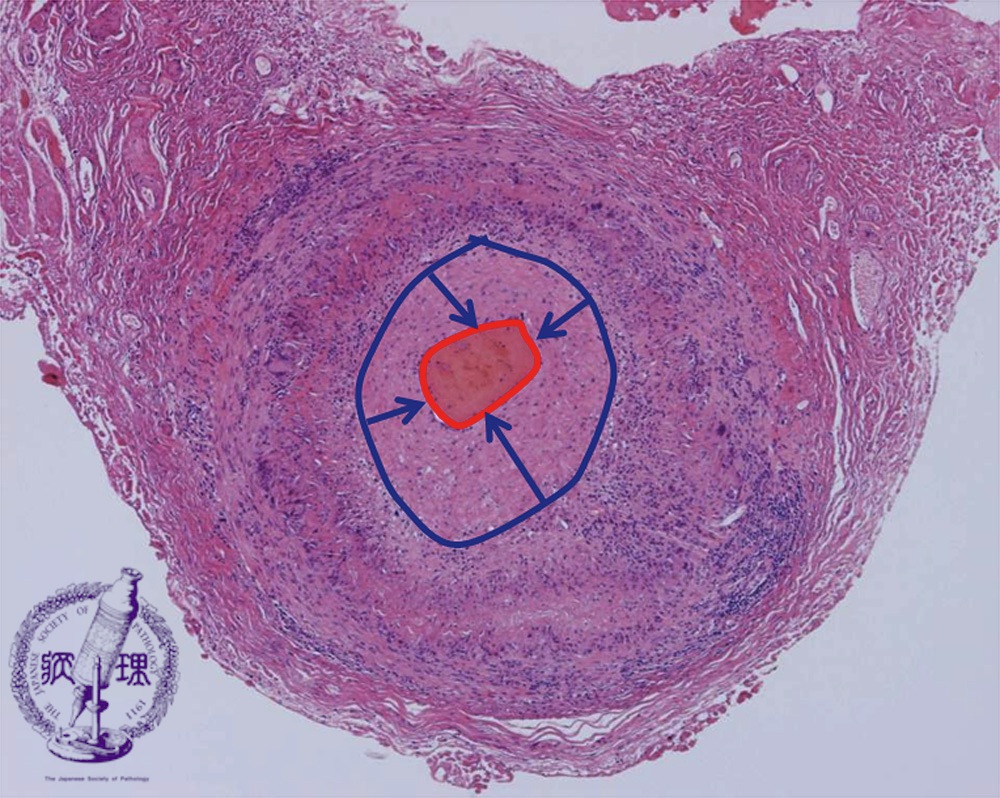

巨細胞性動脈炎 (GCA) は、動脈の内層、最も多くの場合は頭の動脈の炎症です。かなり珍しい病気です。